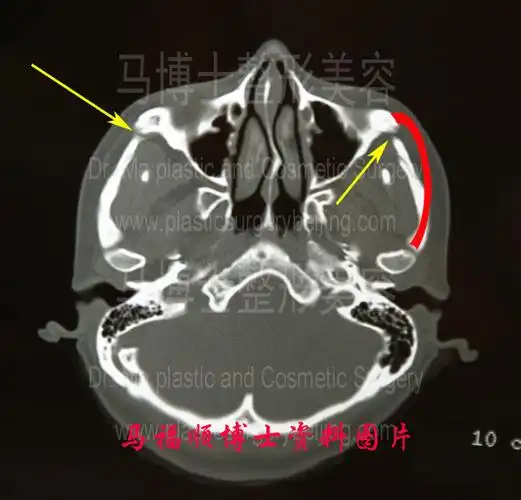

颧骨颧弓前端截骨后ct断层所留下的痕迹

ct】②术中可进行面部年轻化术中可以同步进行韧带筋膜提升,颧弓向上

可以考虑iii代张力带固定·颧骨颧弓缩小术,对颧骨颧弓错位提升后,再